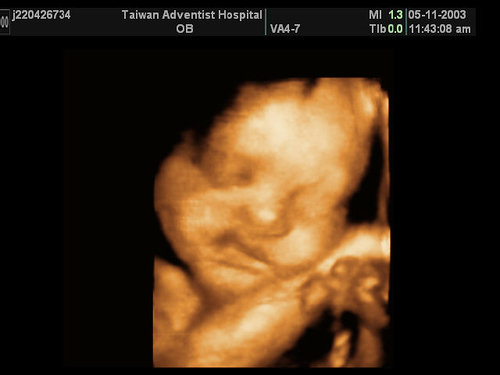

在這一天

我們一家人去醫院跟肚子裡的Omyga見面